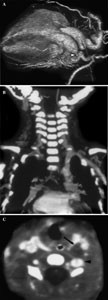

Interrupted Aortic Arch Associated with Absence of Left Common Carotid Artery: Imaging with MDCT

Interrupted aortic arch (IAA) is a rare severe congenital heart defect defined as complete luminal and anatomic discontinuity between ascending and descending aorta. Although its association with various congenital heart defects has been reported, absence of left common carotid artery (CCA) in patients with IAA has not been reported previously. We report a case of IAA associated with the absence of left CCA which was clearly shown on multidetector-row spiral CT.

Figure 1